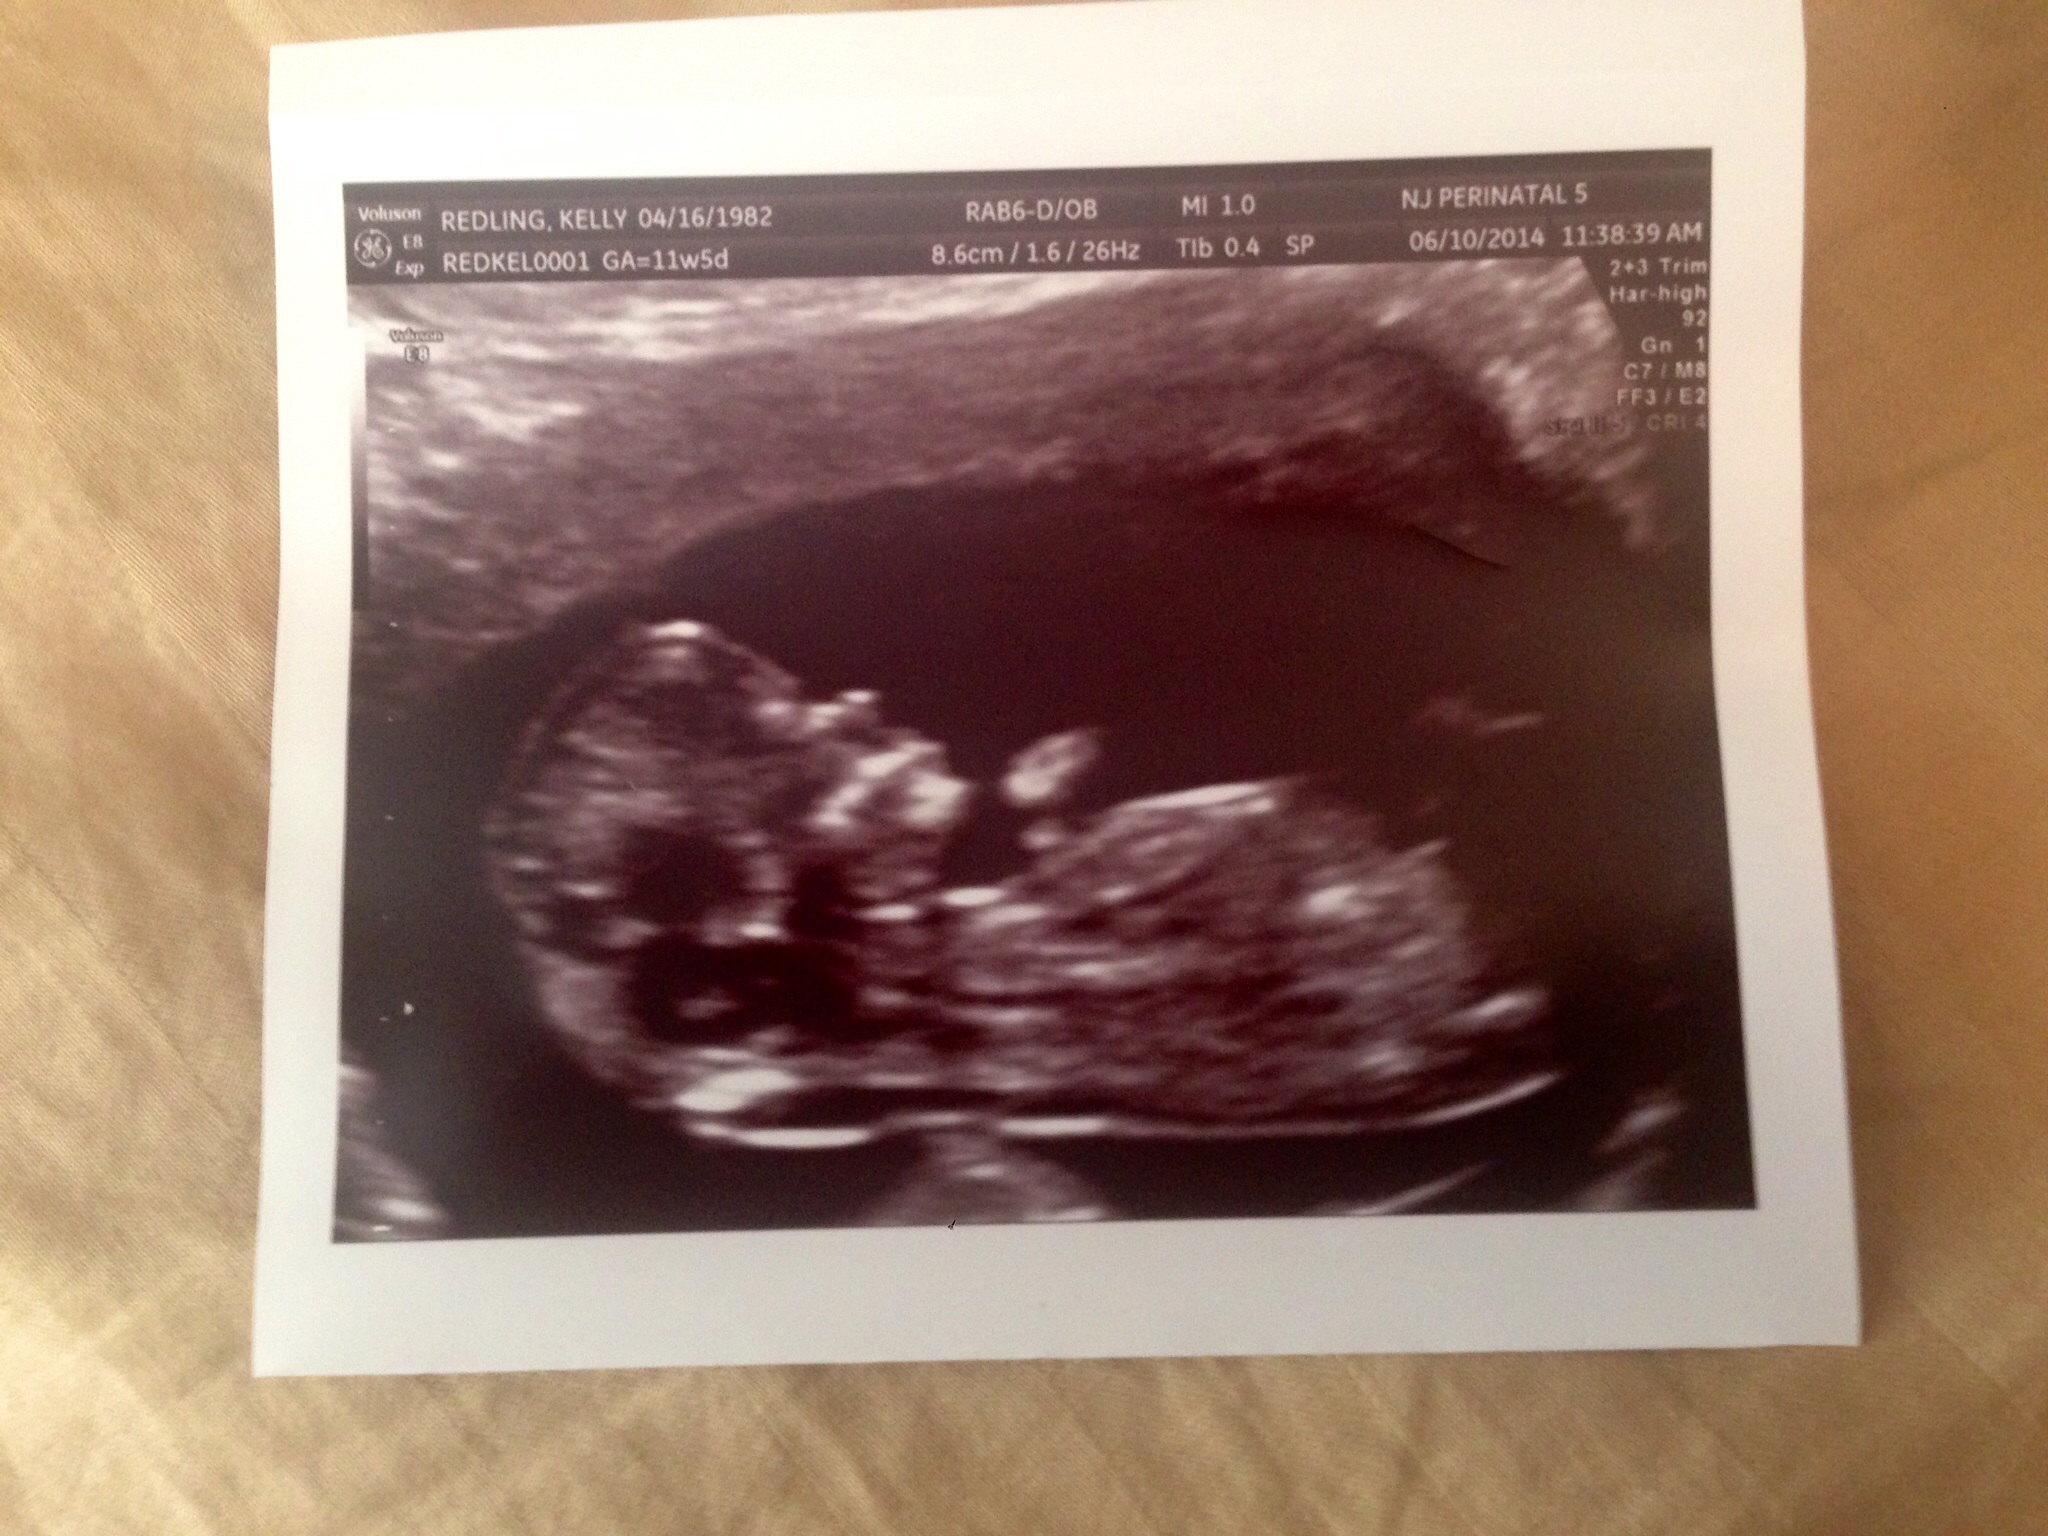

So at my NT scan both the tech and the doctor predicted girl! What do you guys think based off of the skull and nub theory!? I only see the nub in my 3d ultrasound picture. My heart rate has also been between 160-170.